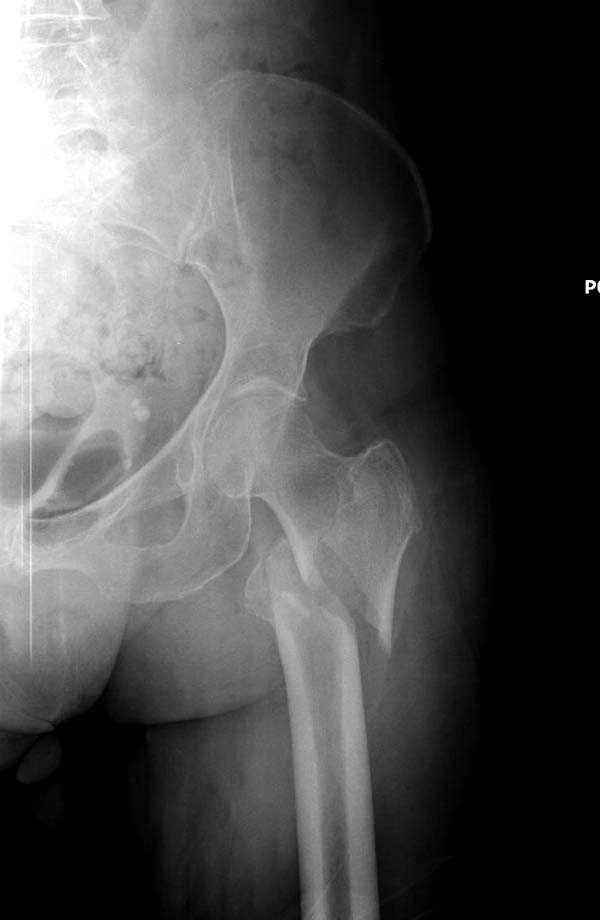

Для лечения переломов проксимального бедра существует различные конструкции, включая цефаломедуллярные. Среди них из-за простоты и удобной конструкции распространенным является Gamma.

Имплант засчет верхней блокировки создает эффект угловой стабильности и применяется не только при скоростных травмах у молодых, а также для лечения переломов пожилого возраста.

Здесь представлен случай, где в послеоперационном периоде обнаружена техническая ошибка, Gamma 3 установлен с нарушением методики. Больная в 91 лет, прооперирована через день после поступления и выписана через 48 часов.

При первом послеоперационном поликлиническом осмотре больная предъявила жалобы на боли в бедре. В серийных снимках обнаружен продольный перелом верхнего отдела бедра.